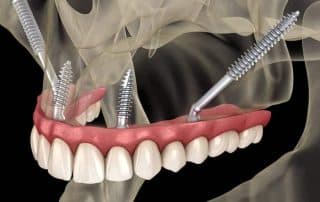

Zigoma implantati

Zigoma oziroma Zygoma implantati so odlična rešitev za vse, ki so ostali brez...